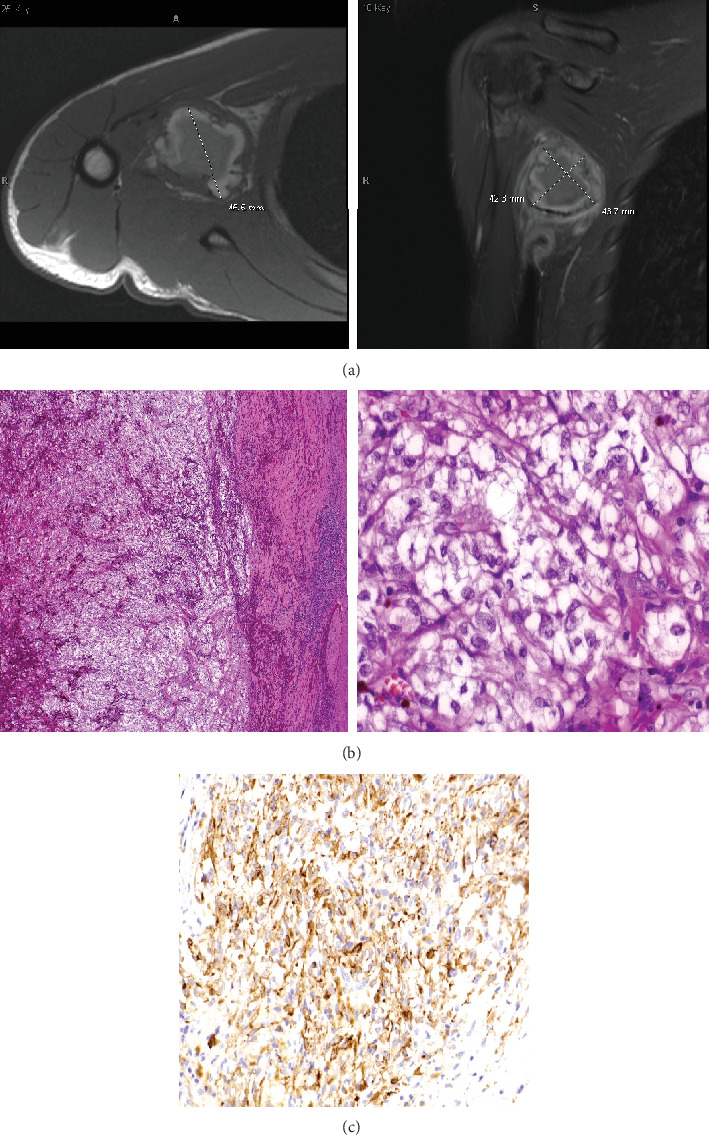

骨与软组织肉瘤包括 70 多种组织学亚型,由于其特征相互重叠,给诊断带来了挑战。荧光原位杂交(FISH)和反转录聚合酶链反应(RT-PCR)等分子分析有助于确定特定的基因组改变,但往往有局限性,尤其是在之前的组织学检查结果不确定的情况下。下一代测序(NGS)通过有针对性的测序面板提供高通量检测,解决了这些局限性。本病例系列着重介绍了 NGS 在诊断两名免疫生物学不明确的尤文肉瘤(ES)和透明细胞肉瘤(CCS)儿科患者中的作用,强调了 NGS 作为实体瘤诊断利器的作用。

Bone and soft-tissue sarcomas encompass over 70 histologic subtypes, posing diagnostic challenges due to overlapping characteristics. Molecular analyses, such as fluorescence in situ hybridization (FISH) and reverse transcription polymerase chain reaction (RT-PCR), aid in identifying specific genomic alterations but are often limited, particularly when prior histological findings are inconclusive. Next-generation sequencing (NGS) offers high-throughput testing via a targeted sequencing panel, addressing these limitations. This case series highlights the utility of NGS in diagnosing two pediatric patients with immunobiologically ambiguous Ewing sarcoma (ES) and clear cell sarcoma (CCS), emphasizing its role as a powerful tool in solid tumor diagnosis.